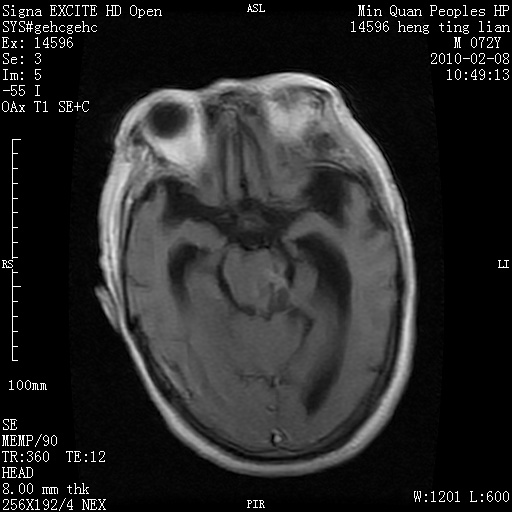

m,72,头疼,头晕两年,伴视力模糊三月,饮食呛咳两天。pe:颈部抵抗,左眼突出,左眼瞳孔约3mm,对光反射消失,双眼失明,伸舌困难,双肺呼吸音粗,心率110次/分,左上肢肌力i级,左下肢屈曲,肌张力高。现有08年2月19mri平扫及10年2月8日mri增强请会诊。ct病灶呈低密度伴散在点、片状等密度区,无明确钙化(无ct片资料可供上传)。[

脑外肿瘤,表皮样囊肿可能性大。

脑外肿瘤,囊实性,环状不规则强化,内听道扩大,考虑神经源性肿瘤

考虑表皮样囊肿。

左侧桥小脑区占位伴梗阻性脑积水----考虑 1神经鞘瘤 2室管膜瘤。

左侧桥小脑区神经鞘瘤伴梗阻性脑积水。

听神经瘤

脑外肿瘤,病灶呈匍匐蔓延,表皮样囊肿可能性大。

脑外肿瘤,病灶呈匍匐蔓延,表皮样囊肿可能性大。支持!

左侧桥脑小脑角区肿瘤并脑积水,考虑听神经瘤,脑膜瘤?

考虑听神经瘤

左侧桥脑小脑角区肿瘤并脑积水,考虑听神经瘤,